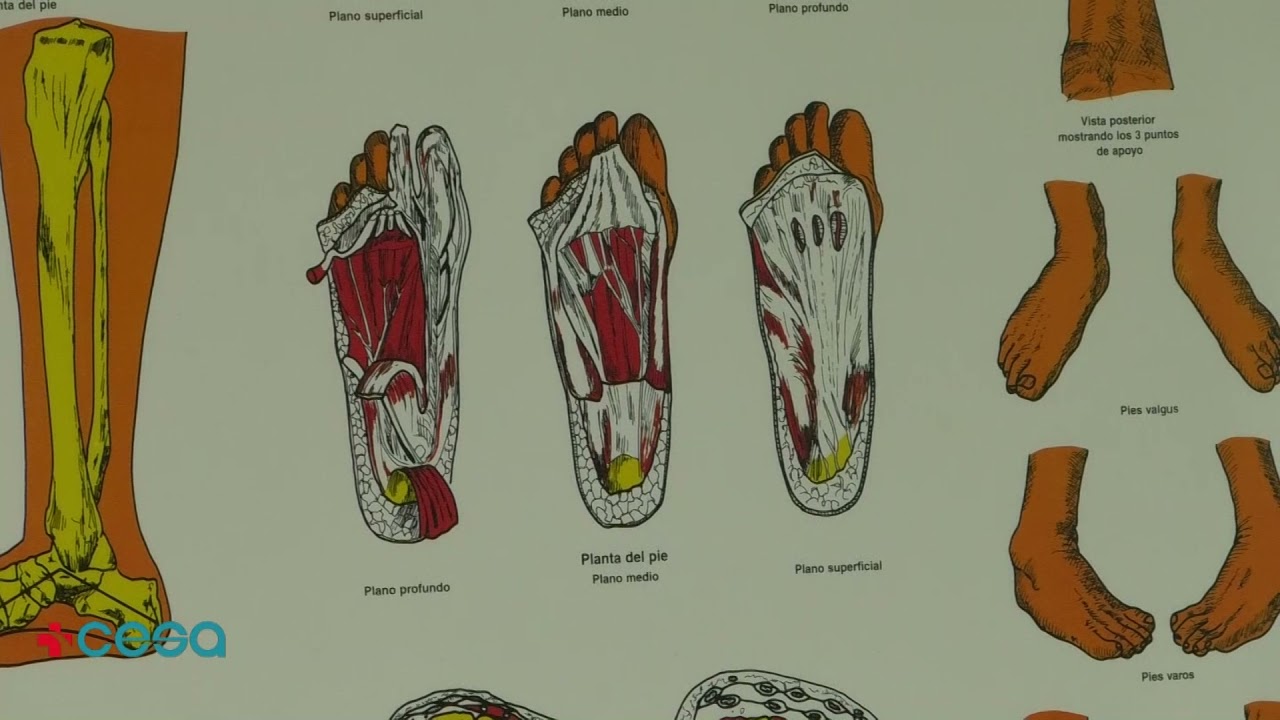

- Podologia riabilitativa di interesse chirurgico

Principali patologie trattate

- Piede cavo

- Sperone calcaneare

- Alluce valgo

Ortesi plantari